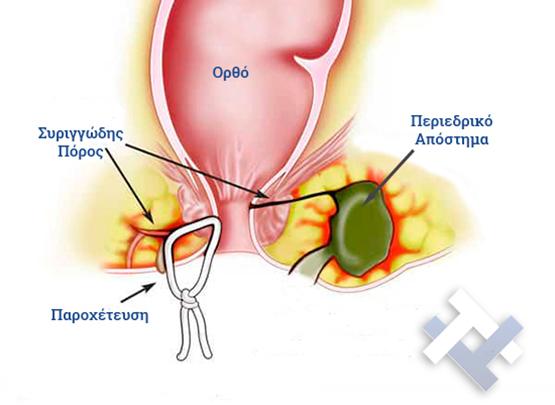

Ο Γενικός Χειρουργός Λιάγκος Γεώργιος MD PhD εκτελεί τις επεμβάσεις Λαπαροσκοπικά, Ενδοσκοπικά, Ανοιχτά Ελάχιστα Επεμβατικά και με Laser. Η θεραπεία εξατομικεύεται σε κάθε ασθενή ανάλογα με τις ανάγκες του. Αναλαμβάνει περιπτώσεις όπως κήλες και κοιλιοκήλες (αντιμετώπιση βουβωνοκήλης, αντιμετώπιση ομφαλοκήλης, θεραπεία επιγαστρικής κήλης, κήλη των αθλητών (Σύνδρομο κοιλιακών προσαγωγών), αντιμετώπιση μετεγχειρητικής κήλης, θεραπεία Μηροκήλης), πέτρες στη χοληδόχο κύστη, λαπαροσκοπική χολοκυστεκτομή, αντιμετώπιση Κύστη Κόκκυγος με λέιζερ (laser), παθήσεις πρωκτού, χειρουργική laser σύγχρονων κυκλικών ινών (αιμορροΐδες αντιμετώπιση, θεραπεία αιμορροϊδων με laser (LHP), αφαίρεση αιμορροΐδων με υπερήχους (HALL-RAR), χωρίς Χειρουργείο με ελαστικούς δακτυλίους (Τεχνική BARON-RBL), θεραπεία ραγάδας πρωκτού (Ραγάδα δακτυλίου), θεραπεία περιεδρικού συριγγίου, θεραπεία περιεδρικού αποστήματος, κονδυλώματα πρωκτού Θεραπεία, δερματικό ράκος (Skin tag) εκτομή, αντιμετώπιση Kνησμού, καρκίνος πρωκτού θεραπεία), παθήσεις Δέρματος, χειρουργική με laser CO2, αφαίρεση μορφωμάτων δέρματος - βιοψίες, αφαίρεση ελιάς (Σπίλου), σμηγματογόνος κύστης θεραπεία, αφαίρεση λιπώματος, είσφρυση όνυχος χειρουργείο, καρκίνος δέρματος θεραπεία, οξεία σκωληκοειδίτιδα, παθήσεις Λεπτού και Παχέος Εντέρου, ειλεός λεπτού εντέρου, εκκολπωμάτωση (Εκκολπωματίτιδα) σιγμοειδούς, καρκίνος παχέος εντέου, κολοστομίες, port χημειοθεραπείας κ.α.

Ο Γενικός Χειρουργός Λιάγκος Γεώργιος MD PhD εκτελεί τις επεμβάσεις Λαπαροσκοπικά, Ενδοσκοπικά, Ανοιχτά Ελάχιστα Επεμβατικά και με Laser. Η θεραπεία εξατομικεύεται σε κάθε ασθενή ανάλογα με τις ανάγκες του. Αναλαμβάνει περιπτώσεις όπως κήλες και κοιλιοκήλες (αντιμετώπιση βουβωνοκήλης, αντιμετώπιση ομφαλοκήλης, θεραπεία επιγαστρικής κήλης, κήλη των αθλητών (Σύνδρομο κοιλιακών προσαγωγών), αντιμετώπιση μετεγχειρητικής κήλης, θεραπεία Μηροκήλης), πέτρες στη χοληδόχο κύστη, λαπαροσκοπική χολοκυστεκτομή, αντιμετώπιση Κύστη Κόκκυγος με λέιζερ (laser), παθήσεις πρωκτού, χειρουργική laser σύγχρονων κυκλικών ινών (αιμορροΐδες αντιμετώπιση, θεραπεία αιμορροϊδων με laser (LHP), αφαίρεση αιμορροΐδων με υπερήχους (HALL-RAR), χωρίς Χειρουργείο με ελαστικούς δακτυλίους (Τεχνική BARON-RBL), θεραπεία ραγάδας πρωκτού (Ραγάδα δακτυλίου), θεραπεία περιεδρικού συριγγίου, θεραπεία περιεδρικού αποστήματος, κονδυλώματα πρωκτού Θεραπεία, δερματικό ράκος (Skin tag) εκτομή, αντιμετώπιση Kνησμού, καρκίνος πρωκτού θεραπεία), παθήσεις Δέρματος, χειρουργική με laser CO2, αφαίρεση μορφωμάτων δέρματος - βιοψίες, αφαίρεση ελιάς (Σπίλου), σμηγματογόνος κύστης θεραπεία, αφαίρεση λιπώματος, είσφρυση όνυχος χειρουργείο, καρκίνος δέρματος θεραπεία, οξεία σκωληκοειδίτιδα, παθήσεις Λεπτού και Παχέος Εντέρου, ειλεός λεπτού εντέρου, εκκολπωμάτωση (Εκκολπωματίτιδα) σιγμοειδούς, καρκίνος παχέος εντέου, κολοστομίες, port χημειοθεραπείας κ.α.